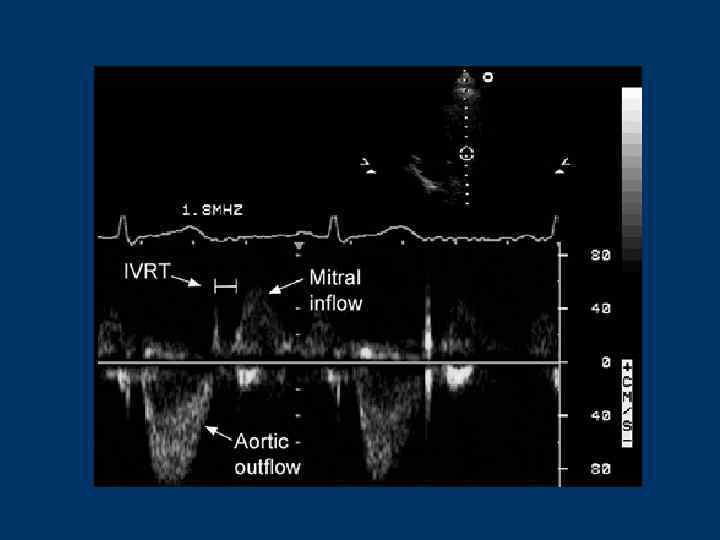

Основные понятия, используемые при проведении допплеровского исследования • АТ (acceleration time) - время ускорения потока определяется от начала до пика кривой, мс • DТ (deceleration time) - время замедления - от пика до окончания кривой, мс • Velocity – скорость потока (м/с, см/с) – максимальная (peak, max) – средняя (mean) • ЕТ (ejection time) - период изгнания - от начала до окончания кривой, мс • VTI (velocity time integral) – площадь под кривой TVI= Velmean х ET • IVRT – время изоволюметрического расслабления • IVСT – время изоволюметрического сокращения